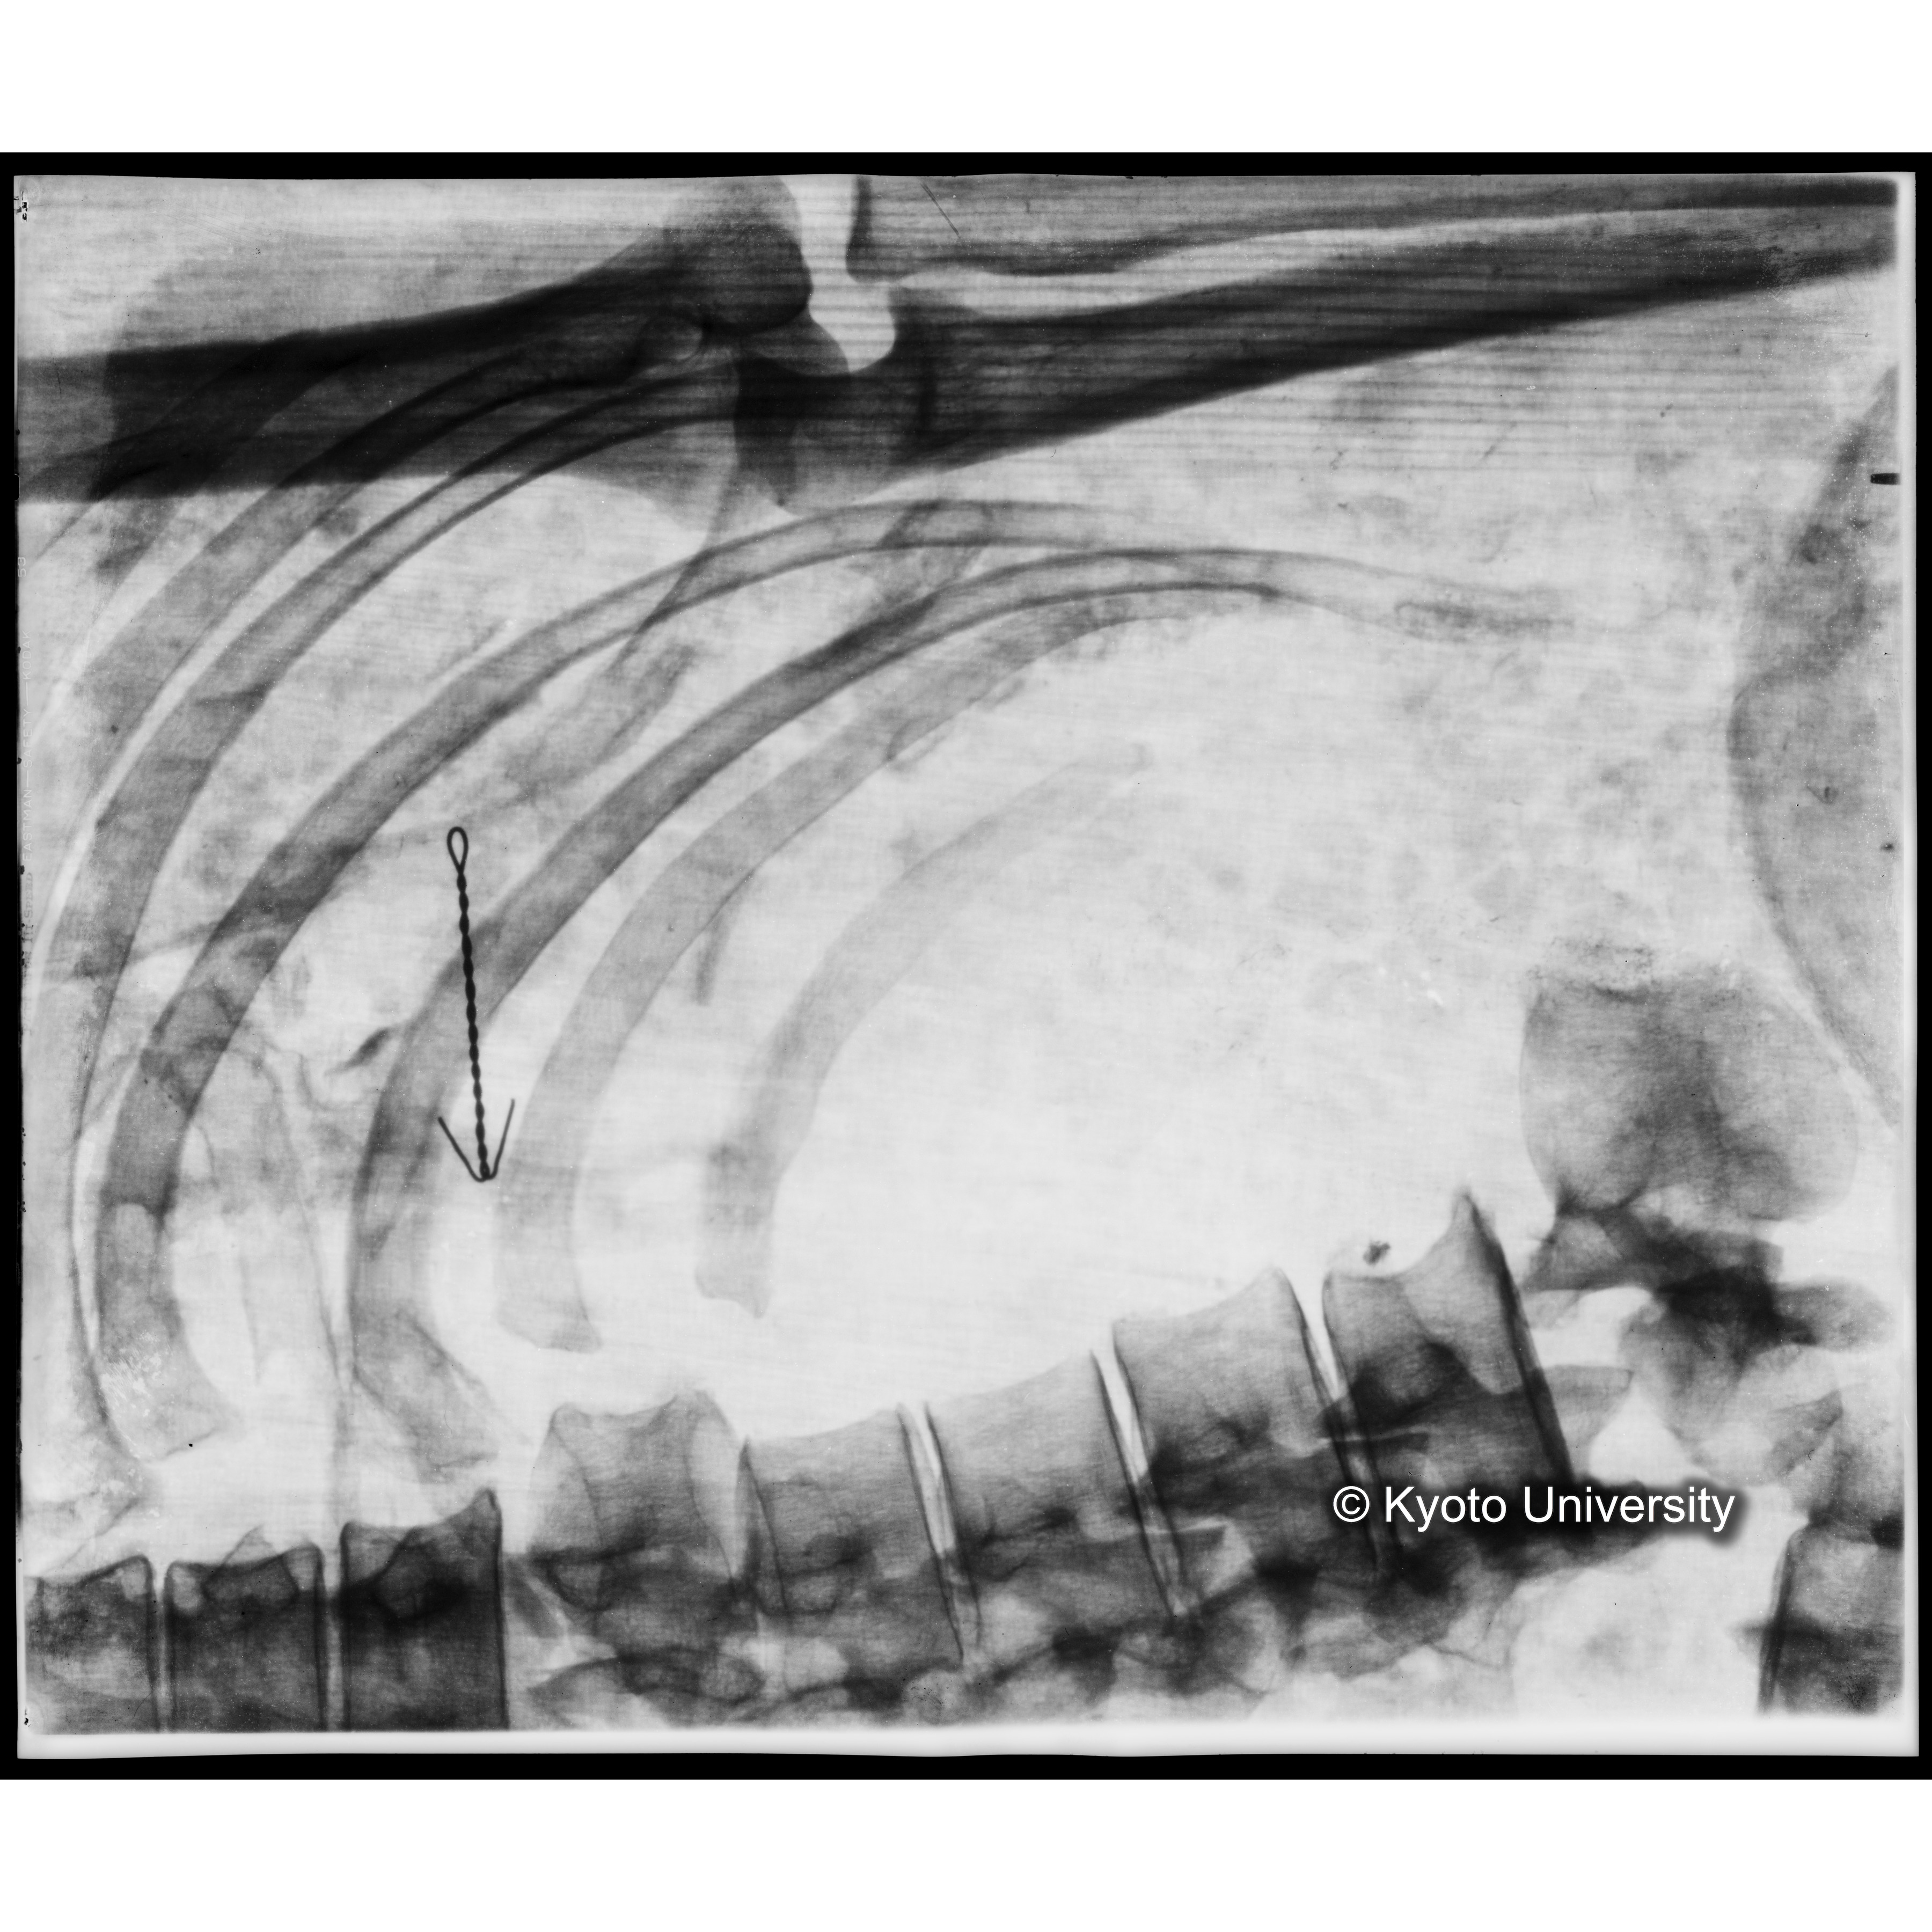

[写真内容] 胸部レントゲン

「蘇った古代の木乃伊-藤原鎌足-」における119頁の「44 胸部レントゲン」にコンテンツを右に90度回転したものが対応している.